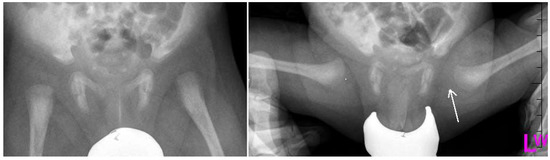

Figure 2.

Radiographs: Antero-posterior (AP) and Lauensteun view of three weeks old child’s left hip, slightly out of the socket (eccentric hip).

Figure 3.

Radiographs: AP and Lauensteun with postrezidual deformity in the same patient after 2 years.